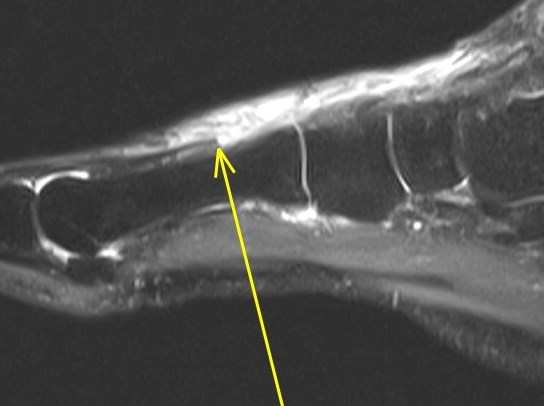

Figure 3 for case Extensor hallucis longus tendon ( RID3188 ) laceration

Figure 3

You can see the cleanly lacerated tendon edges nicely (arrows)